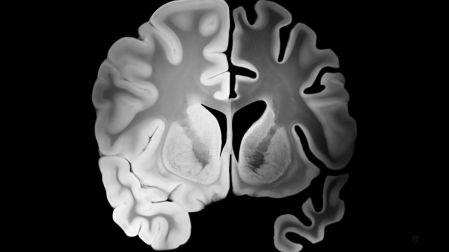

- 69 % menor pérdida de volumen cerebral

Estudios previos con modelos animales ya habían demostrado que esta frecuencia ayudaba a reducir la acumulación de placas beta-amiloides, un marcador clave del Alzheimer. Este nuevo ensayo en humanos valida esos hallazgos preliminares con métricas objetivas.